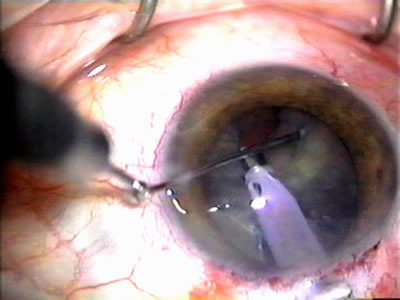

The inflammation associated with lens extraction at any site usually causes complete failure of a marginal functioning bleb. In addition, pressure reduction by medical means is usually minimal in these recalcitrant cases, and combined surgery is indicated. In the past, these cases were approached with large-incision ECCE, clear corneal cataract incision, and bleb revision. Drawbacks included those mentioned earlier for large incision clear corneal cataract extraction, and bleb revision is often associated with conjunctival buttonholes, wound leaks, subconjunctival hematoma, destruction of friable sclera, and associated hypotony. With the advent of modern-day cataract surgery, a phacotrabeculectomy is often possible adjacent to the failed filter (Fig. 7). The ability to combine cataract extraction with implant and filtration surgery all through the same small incision has greatly improved outcomes for patients with marginal preoperative filters. There are several other viable options in this case. If the surgeon elects to remove the cataract through a temporal clear corneal incision, the bleb may be revised or a new adjacent filter fashioned. As mentioned earlier, revising a failed filter is technically challenging. If the surgeon believes it is not feasible to revise the filter or fashion a new one, a glaucoma drainage implant is a reasonable option combined with temporal lens extraction.172

Fig. 7. Phacotrabeculectomy adjacent to a failed filter in cataractous eye. The ability to combine small-incision cataract extraction with trabeculectomy all through the same incision adjacent to the failed filter allows the surgeon to work in a familiar superior area. Avoiding incisions into the existing bleb decreases conjunctival buttonholes, hypotony, operating room time, and subconjunctival bleeding. A. Appearance of failed bleb with exposure of superior temporal quadrant gained with a corneal traction suture. B. Prepare a limbus-based conjunctival flap and a scleral flap. C. This bleb is at high risk to fail again justifying the need for MMC, 0.2 mg/cc applied on a pledget for 4 minutes. D. Insert the keratome and perform phacotrabeculectomy in the usual fashion.